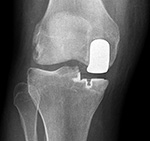

| Unicompartmental knee prosthesis placed in the medial compartment (AP view) |

Unicompartmental knee prosthesis placed in the medial compartment (lateral view) |

Unicompartmental knee prosthesis placed in lateral knee compartment |

| From Taljanovic, 2005 |

50 year-old man with lateral knee compartment degenerative osteoarthritis |